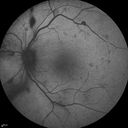

Proliferative Diabetic Retinopathy - Moderate - mild NVD with NVE 405 viewsFA shows leakage from neovascularization and dark areas in periphery from non-perfusion     (0 votes)

Proliferative Diabetic Retinopathy - Moderate - mild NVD with NVE 483 viewsFA shows leakage from neovascularization and dark areas in periphery from non-perfusion     (0 votes)